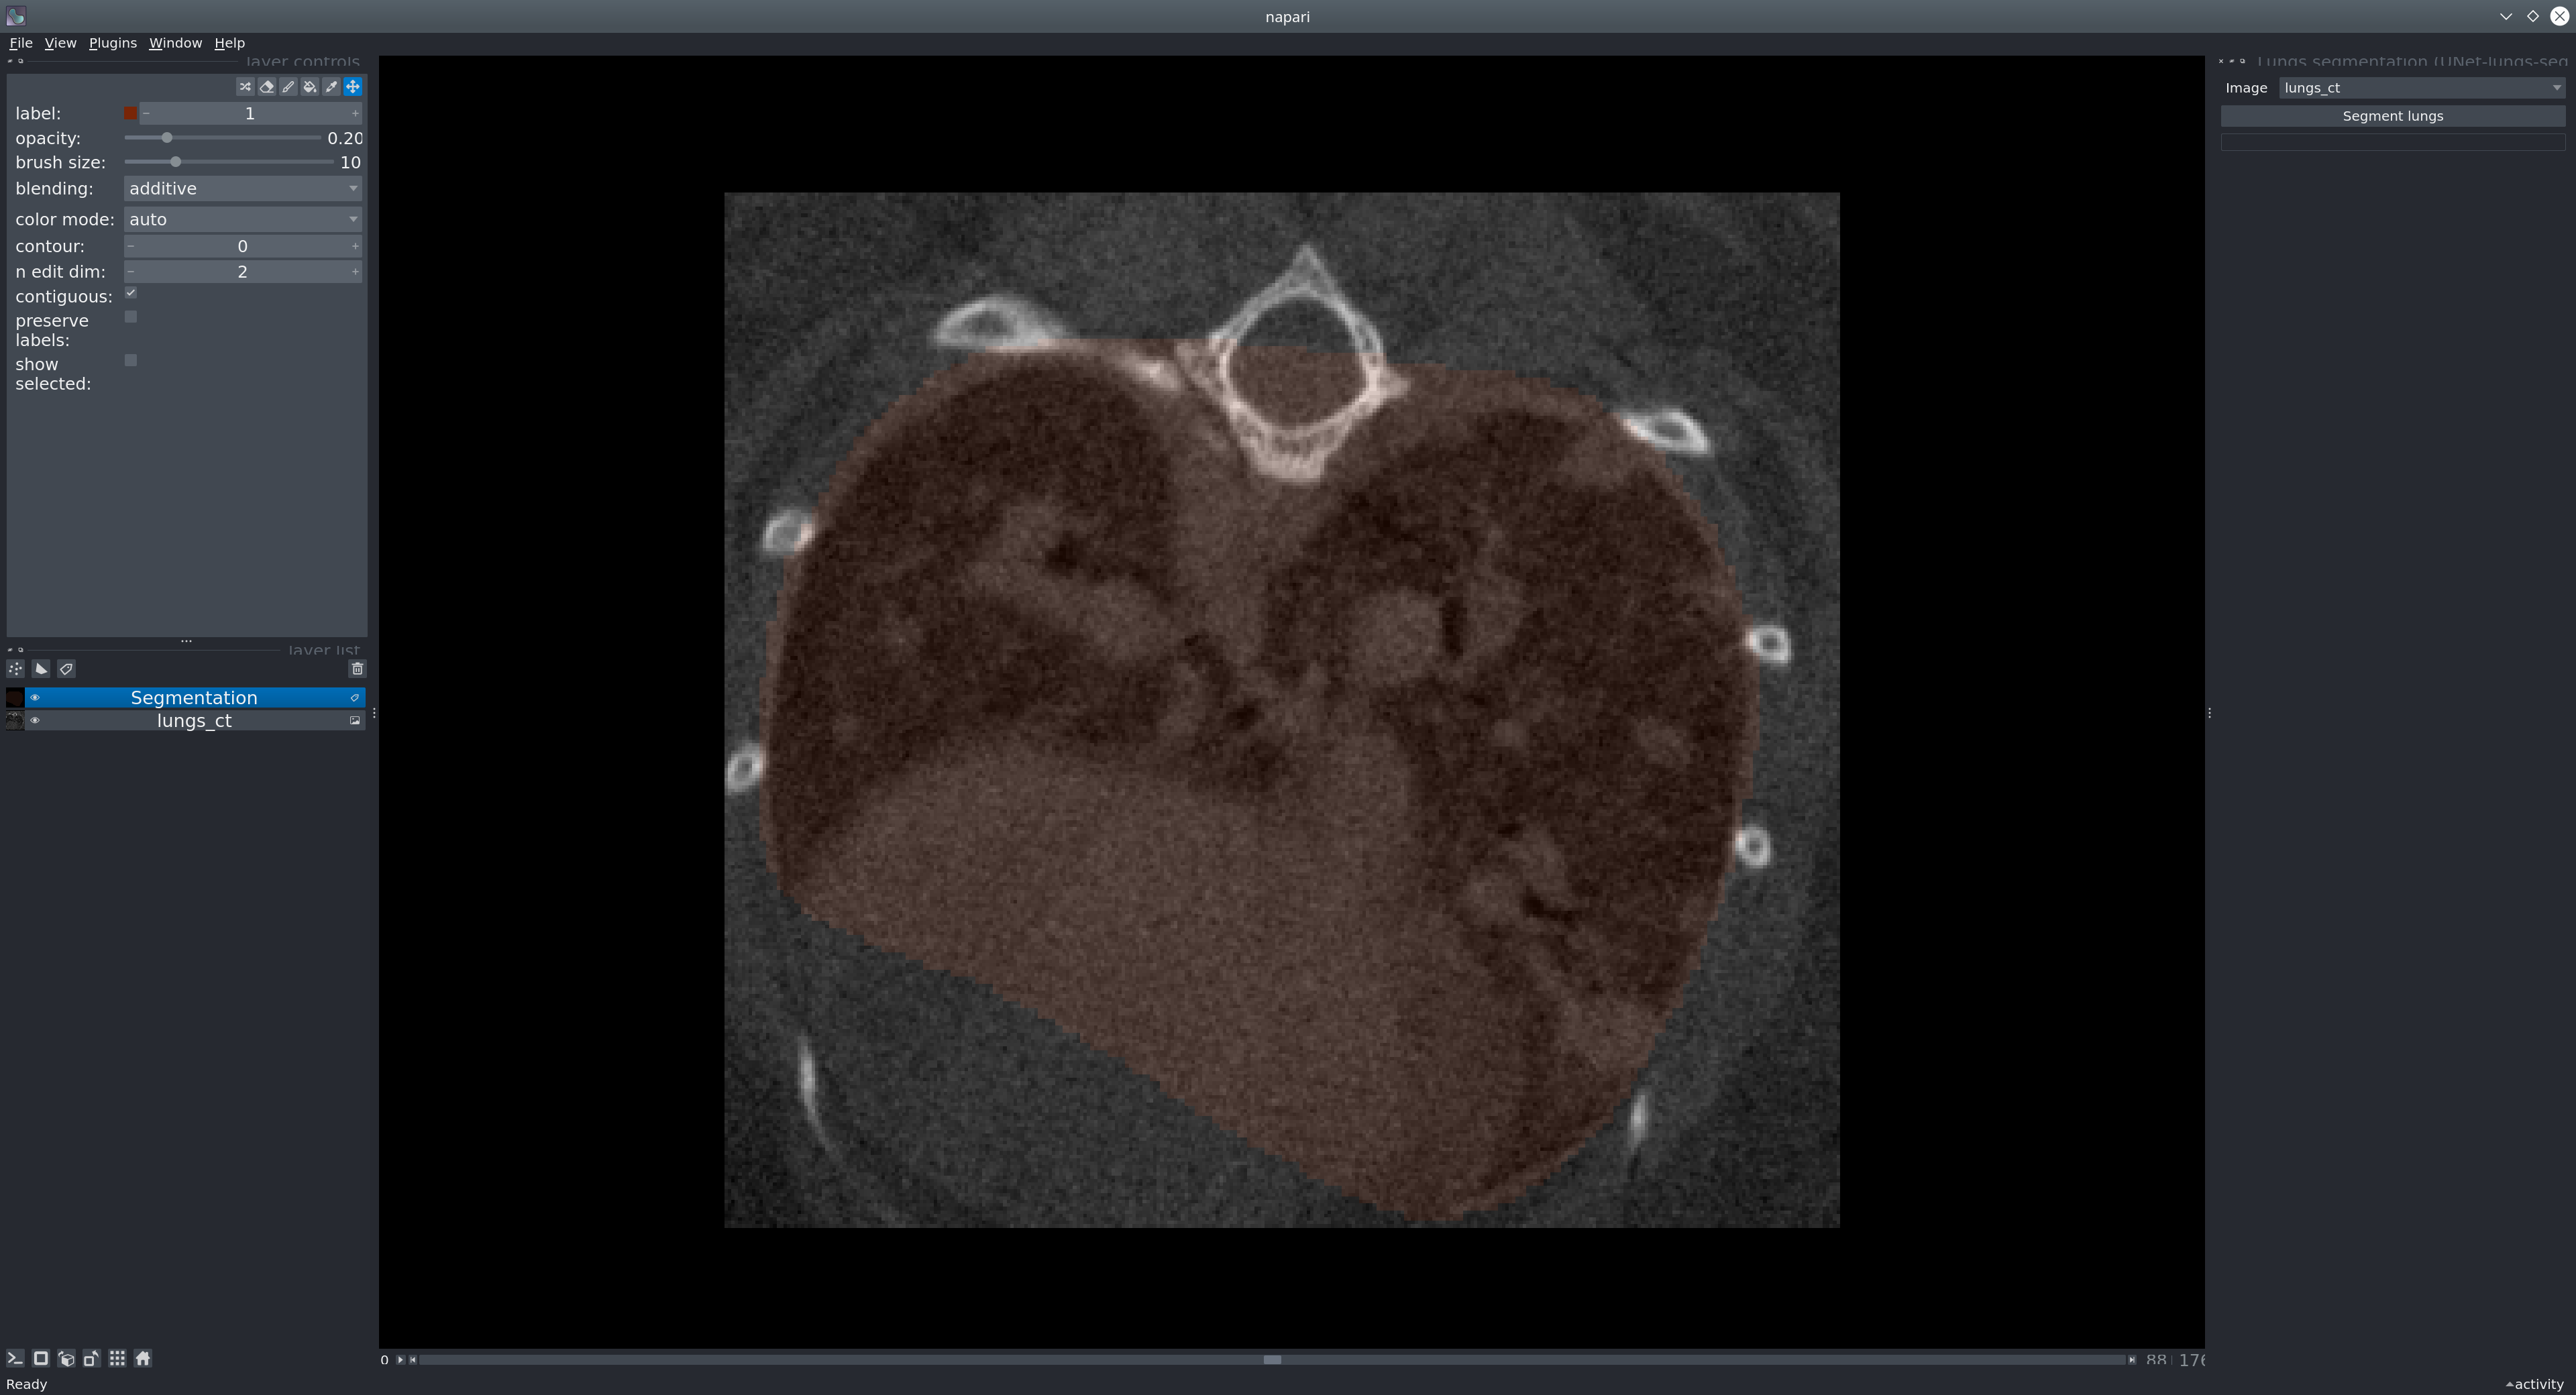

Usage in Napari

Napari is a multi-dimensional image viewer for python. To use our model in Napari, start the viewer with

napari

To open an image, use File > Open files or drag-and-drop an image into the viewer window. If you want to open medical image formats such as NIFTI directly, consider installing the napari-medical-image-formats plugin.

Sample data: To test the model, you can run it on our provided sample image. In Napari, open the image from File > Open Sample > Mouse lung CT scan.

Next, in the menu bar select Plugins > Lungs segmentation (unet_lungs_segmentation). Select an image and run it by pressing the "Segment lungs" button.